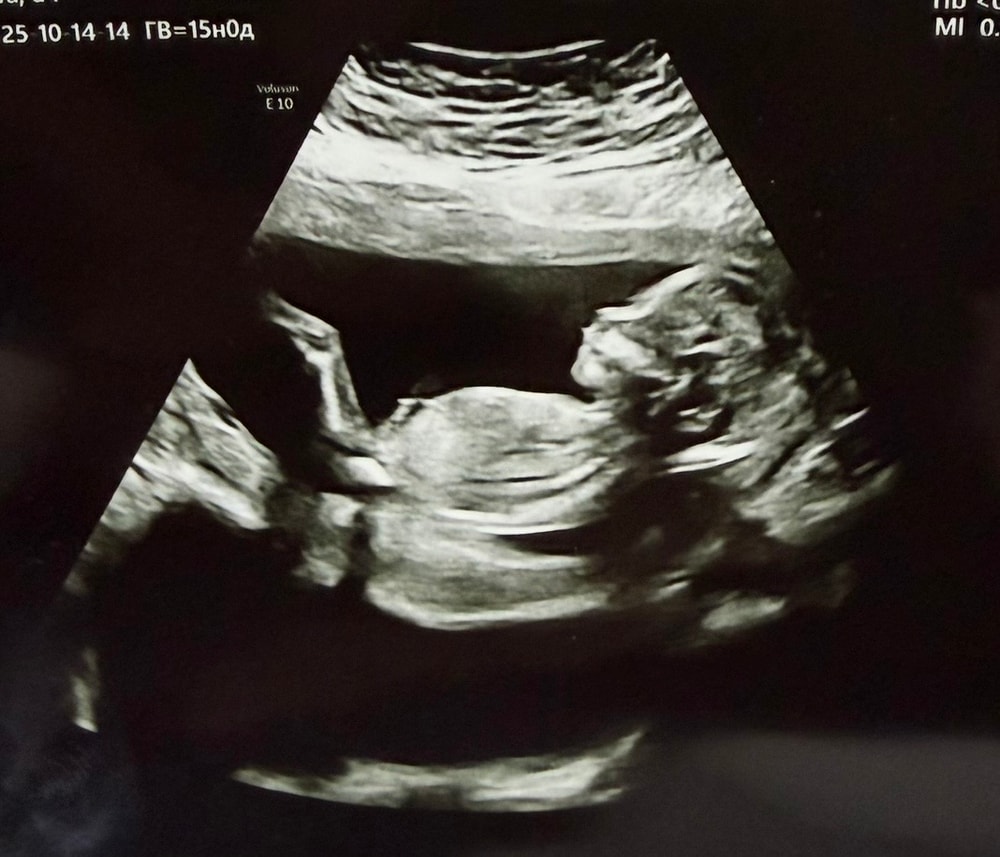

вчера вечером лежа на кровати впервые ощутила легкие копошения и толчки🥹🫣 Божечки, это так волнительно и трепетно было🥹 анализы плановые осмотры итп все хорошо🙌🏻 а так, конечно, я пошла бы на УЗИ в энный раз😝😂 но потерплю до 2 скрининга🫠 ой кстати давление у меня повышенное либо оно всегда было таким либо сейчас так стало с 🤰🤷♀️ вчера ку